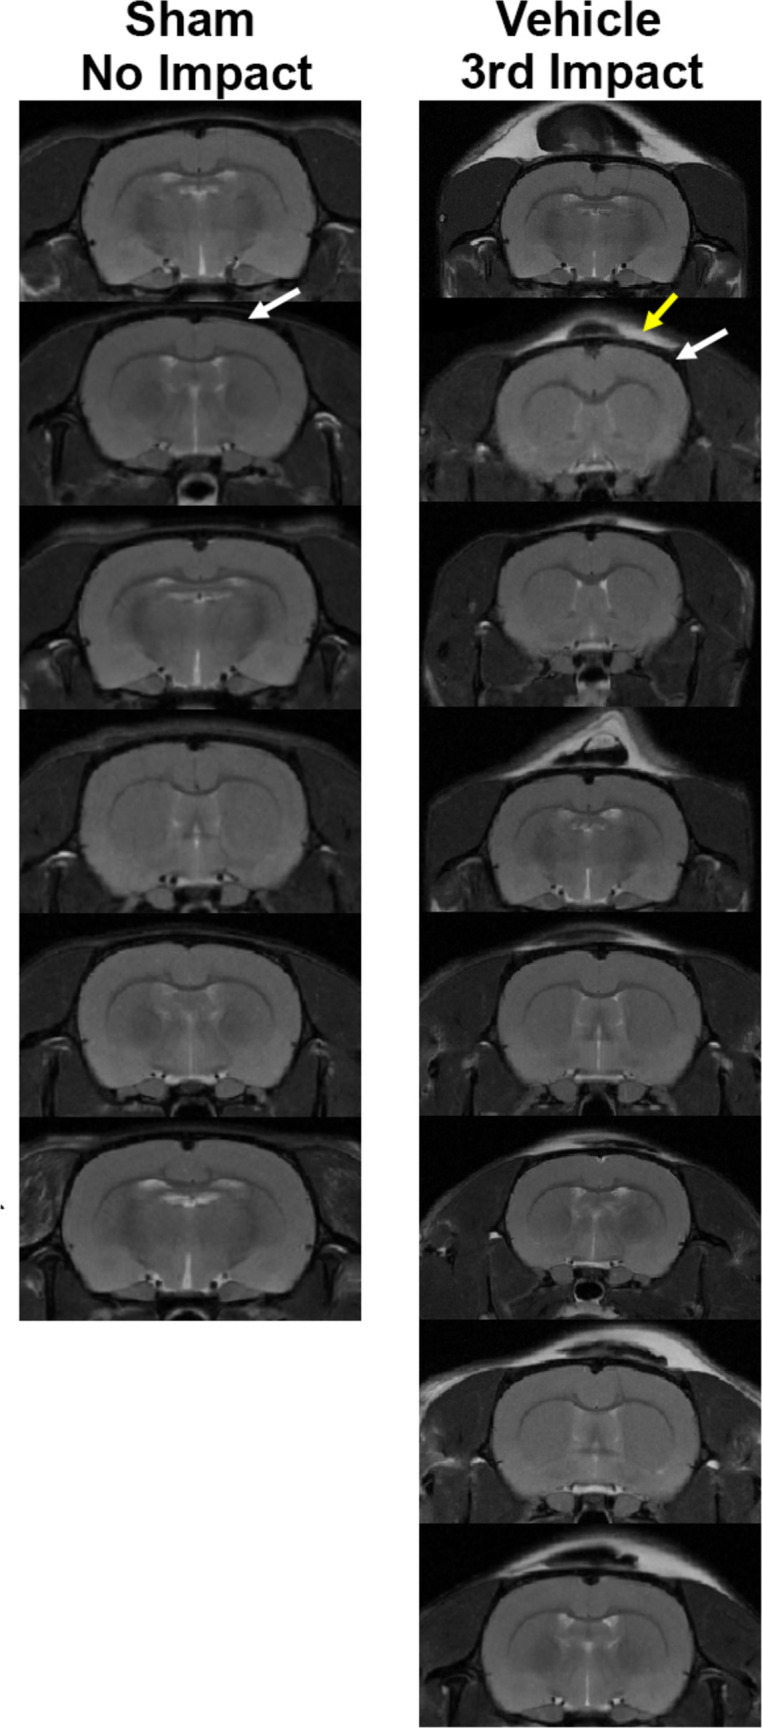

Mild repetitive head injury is a serious health problem with long-term negative consequences. Changes in brain neurobiology were assessed with MRI in a model of head injury designed to reflect the human experience. Rats were maintained on a reverse light-dark cycle and head impacted daily at 24 h intervals over three days while fully awake under red light illumination. There was no neuroradiological evidence of brain damage. Rats were imaged for changes in blood brain barrier permeability, edema and gray matter microarchitecture, and resting state functional connectivity. Data were registered to a 3D MRI rat atlas with 173 segmented brain areas providing site-specific information on each imaging modality. Changes in BBB permeability were minimal and localized to the hippocampus and cerebellum. There was evidence of cytotoxic edema in the basal ganglia, thalamus, and cerebellum. There was a global decrease in connectivity and an increase in gliosis in the thalamus, cerebellum, and hippocampus. This study shows a sequelae of neuropathology caused by mild repetitive head injury that is commonly observed in clinical practice using MRI in patients. As such, it may serve as a model for testing the efficacy of new therapeutics using any or all of the measures as biomarkers to assess drug efficacy.